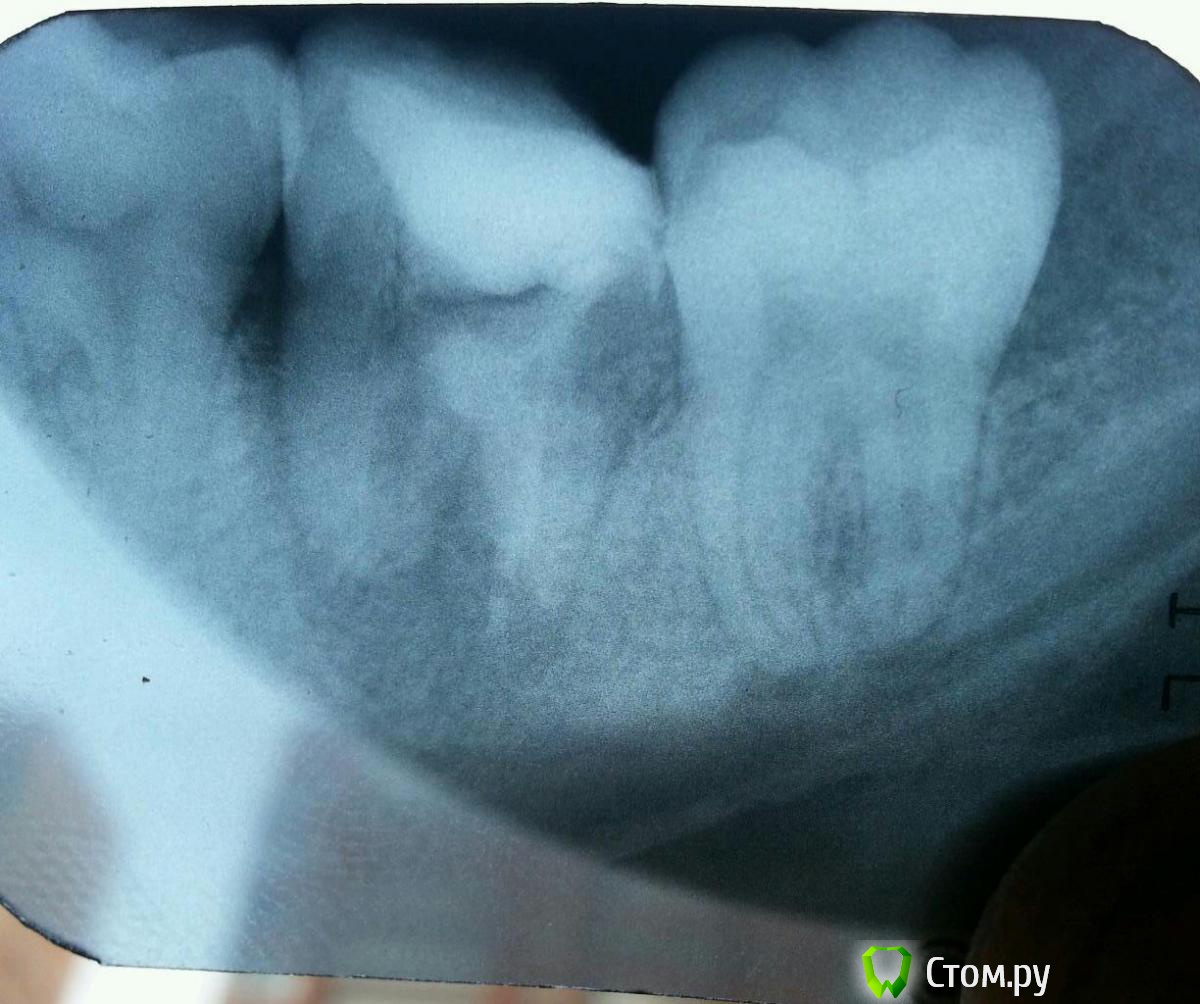

Oleg_90 Опубликовано 23 сентября, 2014 Автор Поделиться Опубликовано 23 сентября, 2014 1-й снимок сделан 31.01.14, когда первый раз пломбировали2-й - 21.08.14 чистили каналы3-й - сегодня Ссылка на комментарий